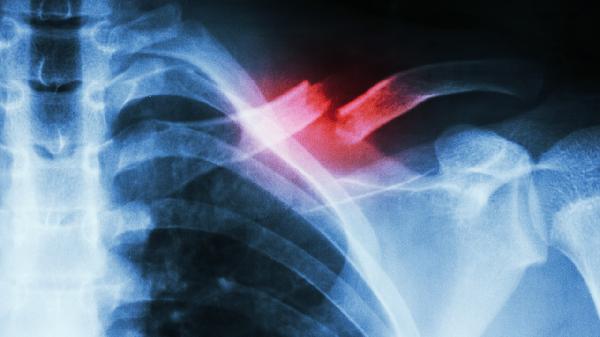

剧烈运动或突然扭转可能导致胸锁乳突肌或胸大肌拉伤,表现为局部压痛和活动受限。急性期可冷敷缓解肿胀,48小时后热敷促进血液循环。避免提重物或过度扩胸动作,通常1-2周可自愈。若疼痛持续加重,需排除肋骨骨折可能。

2、肋软骨炎

肋软骨与胸骨连接处无菌性炎症常由病毒感染或反复微损伤引发,特征为按压痛且咳嗽时加剧。可遵医嘱使用双氯芬酸钠缓释片、塞来昔布胶囊等非甾体抗炎药,配合局部涂抹氟比洛芬凝胶贴膏。睡眠时保持半卧位有助于减轻胸廓压力。